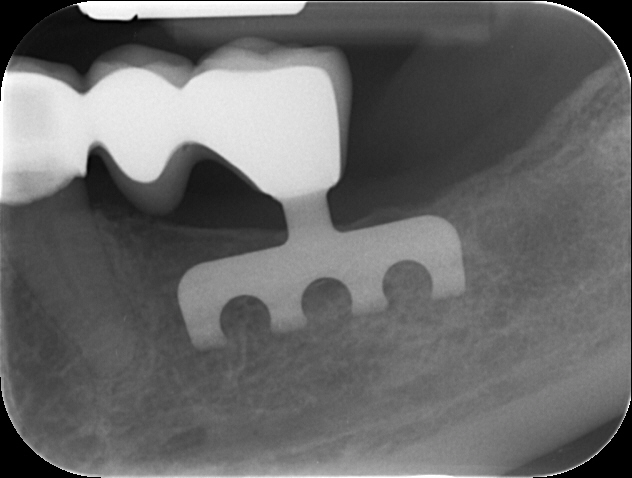

- zavádění čepelkových implantátů